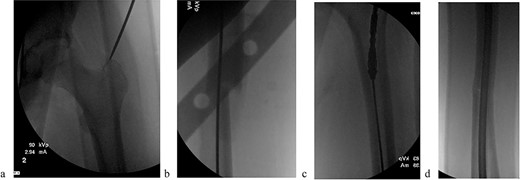

The patient underwent sequential bilateral trochanteric entry antegrade femoral intramedullary rods (Stryker, Kalamazoo, MI, USA) after utilizing bilateral RIAs. We first passed the 8.5-mm end-cutting reamer from the RIA system (DePuy Synthes, Solothurn, Switzerland) and then upsized to an 11.5-mm reamer (Fig. 3a–d). We used the same reamers to prepare the contralateral side.

(a) Obtaining greater trochanteric entry starting point. (b) Fracture reduction with the “F” tool and passed ball-tipped guidewire. (c) Sequentially reaming with the RIA. (d) Maintained fracture reduction with implanted rigid femur rod.